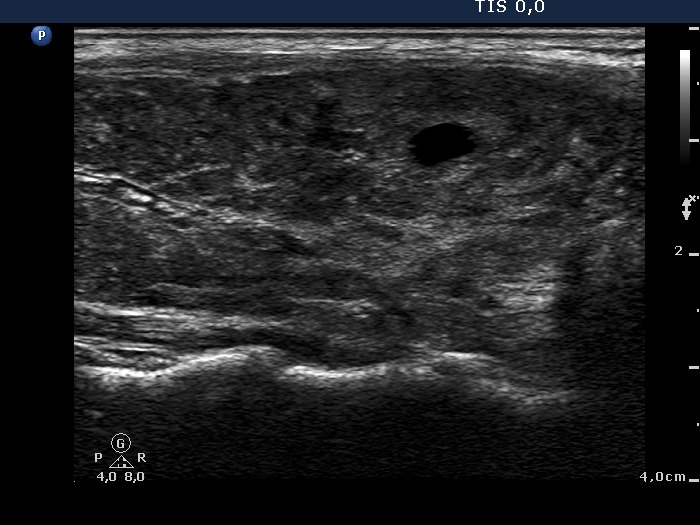

Case 974 (ultrasonographic picture 7)

Lower part of the left lobe, longitudinal scan.